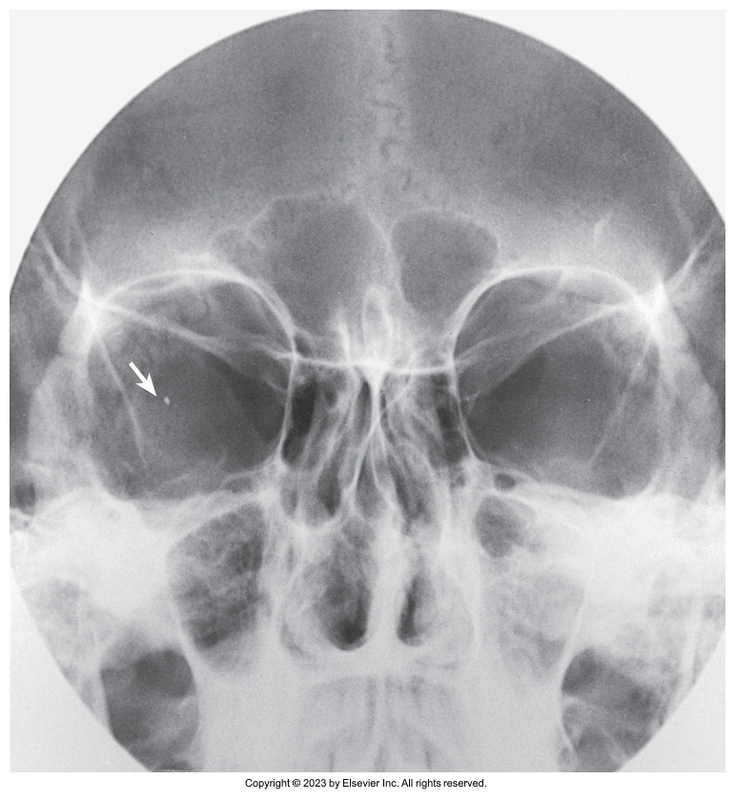

Parietoacanthial of facial bones - Waters method

Parietoacanthial of facial bones - Waters Method